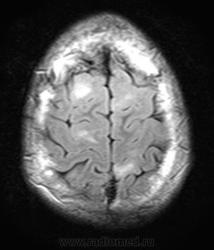

Это болезнь Бурневилля - одна из форм факоматозов?

Да, это болезнь Бурневилля-Прингла, один из видов факоматоза. Врожденное заболевание, развивается из-за нарушений в одной из хромосом.

На УЗИ выявлены множественные ангиомиолипомы почек.